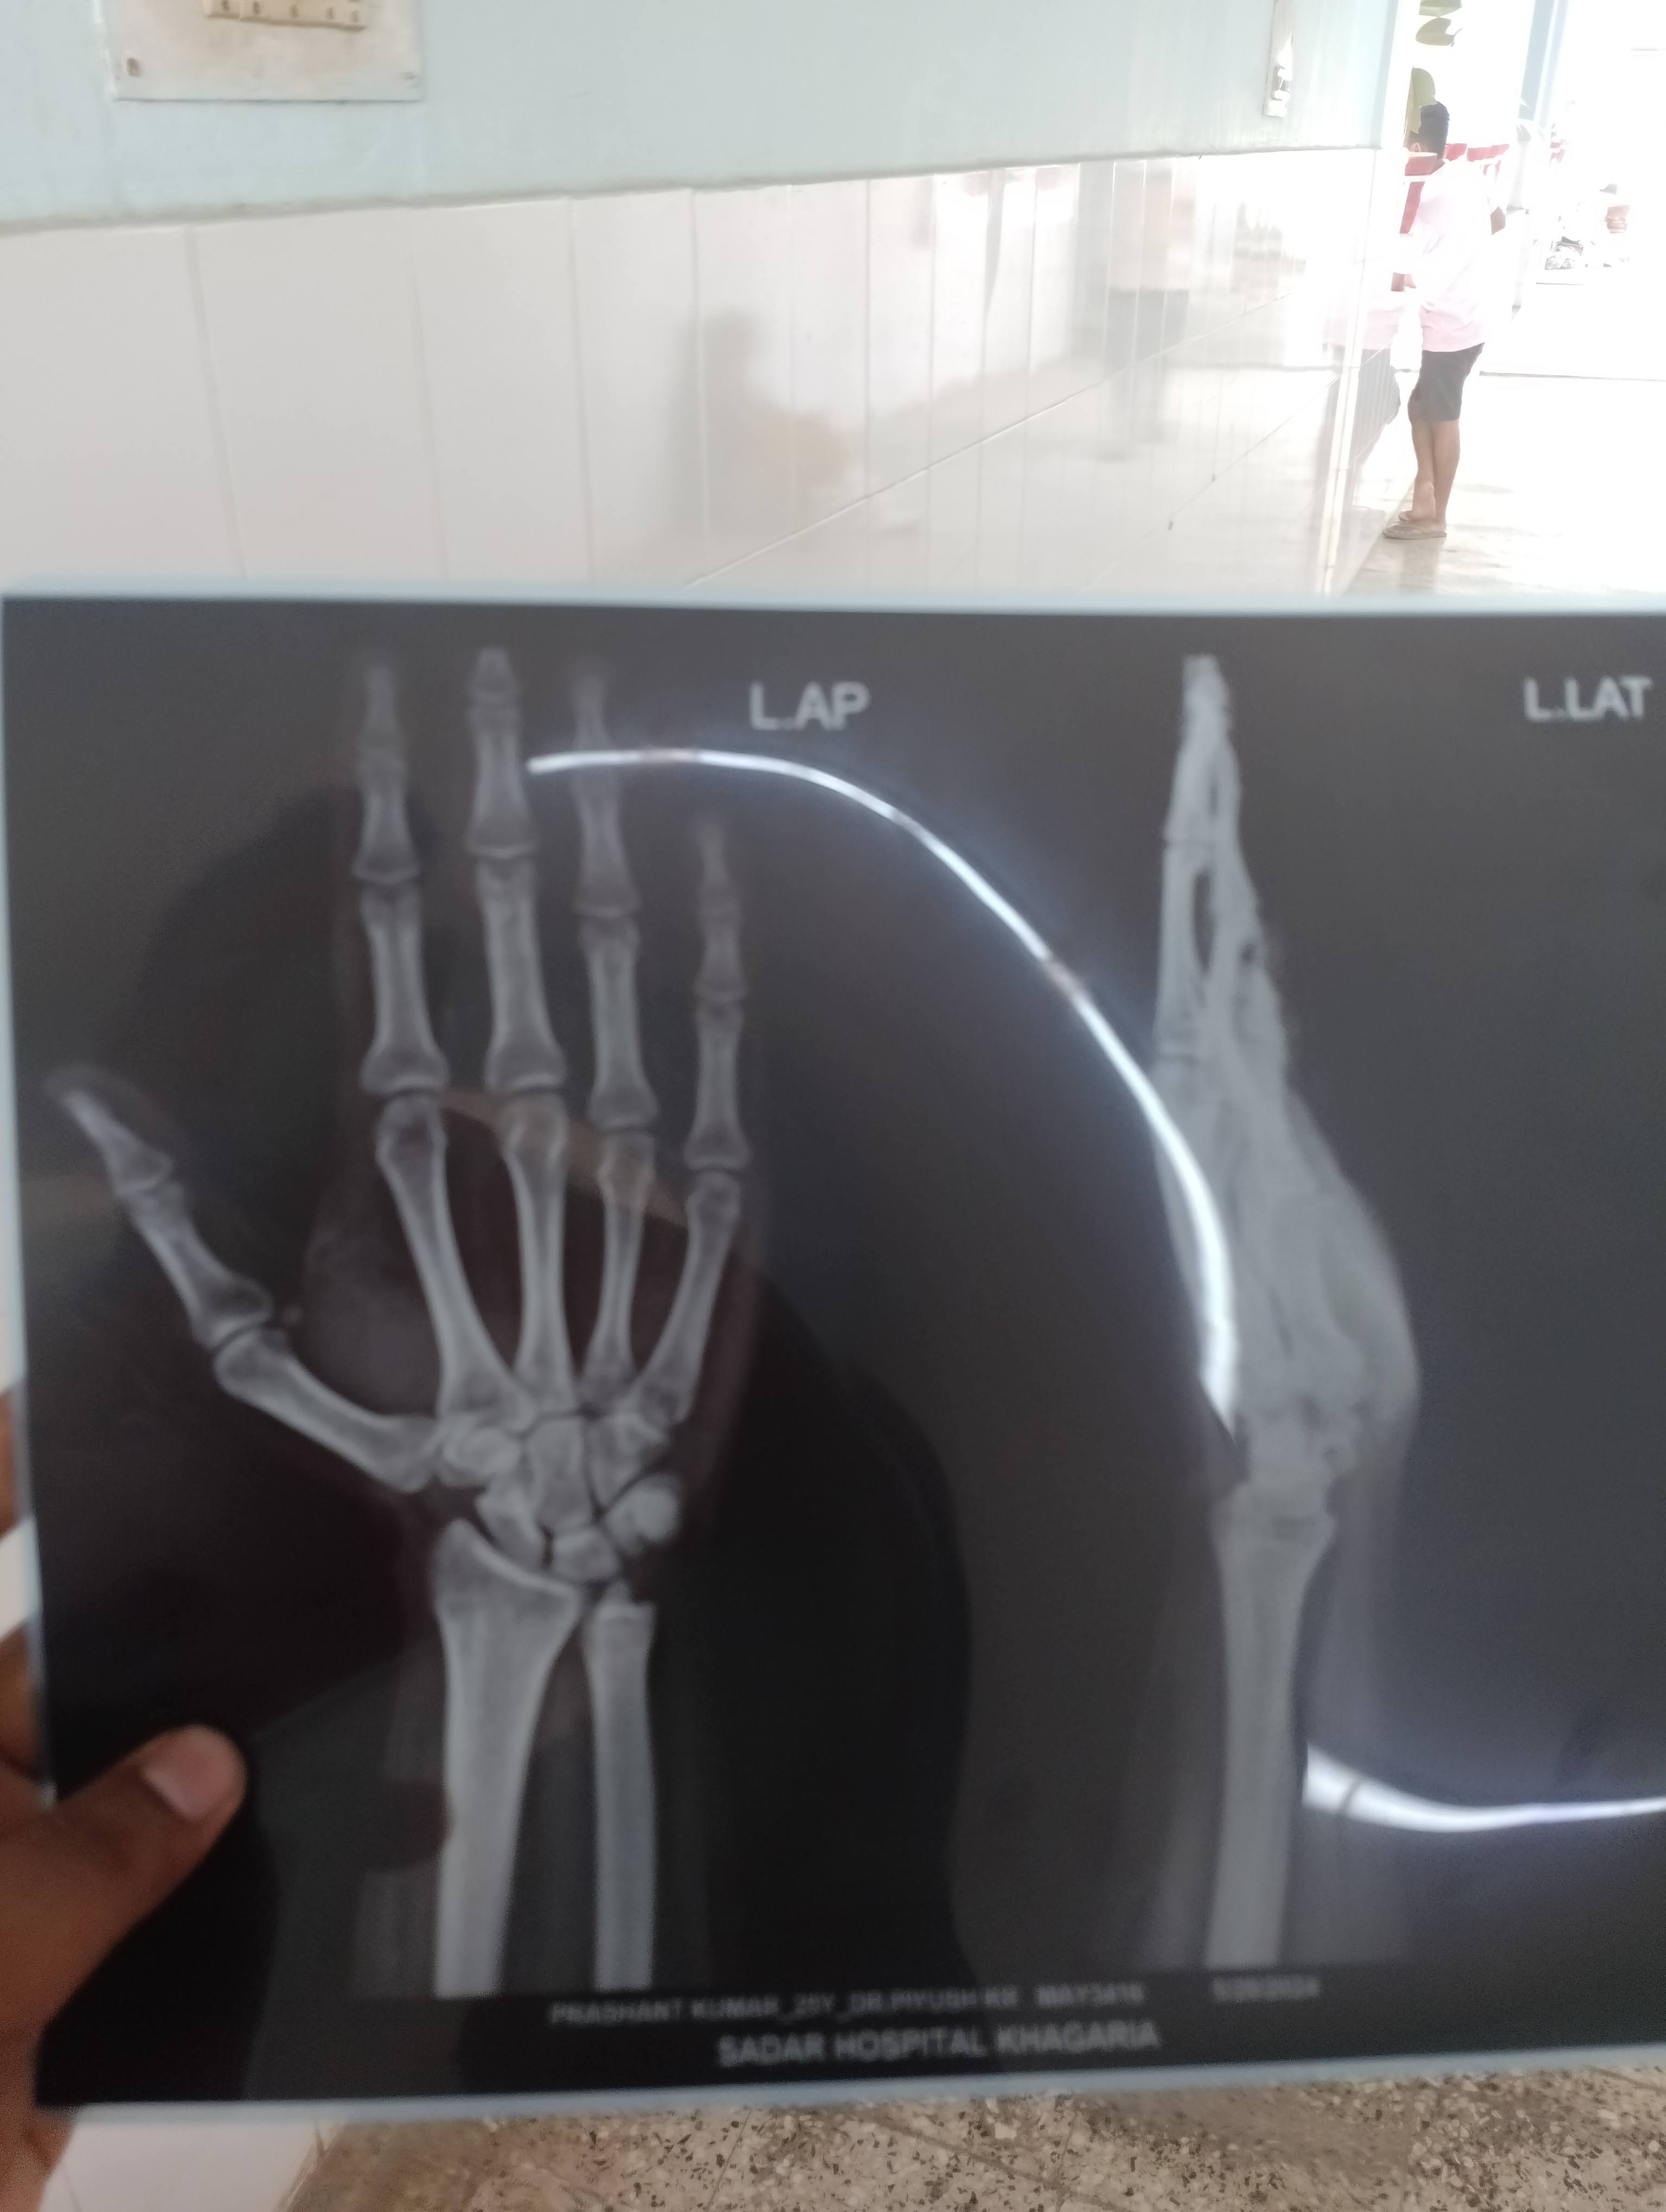

Prashant kumar